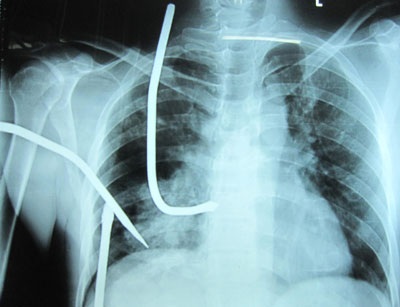

(Dân trí) - Ngày 18/8, bệnh nhân T.Đ.M (43 tuổi ở Nam Định) được chuyển tới BV Việt Đức trong tình trạng bị một cây đinh ba đã đâm lọt vào khoang ngực, nhưng bệnh nhân đã may mắn thoát chết.

“Trong ngực bệnh nhân chảy rất nhiều máu, bị rách thủng phổi phải. 3 cây đinh ngập trong khoang ngực là 6cm. Với những tổn thương ở ngực như thế, nếu không cấp cứu kịp thời hay đường đi của thanh sắt quá hiểm thì bệnh nhân có thể tử vong bất kỳ lúc nào”, BS Lư nói.

Vợ bệnh nhân cho biết, do mẫu thuẫn cá nhân anh M bị người khác dùng đinh ba tấn công và đâm trực diện vào ngực. Theo các bác sĩ, đây là một tai nạn hy hữu và rất may bệnh nhân còn sống đến viện. Thông thường nếu người đâm hoặc người nhà bệnh nhân rút ba thanh sắt này ra thì nguy cơ bệnh nhân sẽ tử vong ngay tại chỗ. Còn hiện tại, sức khỏe của bệnh nhân đã tạm thời ổn định, đang được theo dõi và điều trị tiếp.